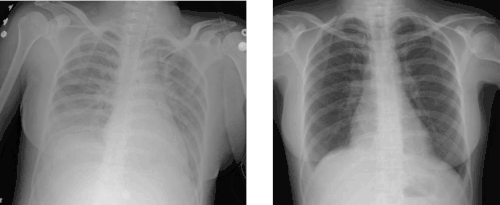

Medical imaging

Radiologic imaging has long been a criterion for diagnosis of ARDS. Original definitions of ARDS specified that correlative chest X-ray findings were required for diagnosis, the diagnostic criteria have been expanded over time to accept CT and ultrasound findings as equally contributory. Generally, radiographic findings of fluid accumulation (pulmonary edema) affecting both lungs and unrelated to increased cardiopulmonary vascular pressure (such as in heart failure) may be suggestive of ARDS. Ultrasound findings suggestive of ARDS include the following:

Diagnostic criteria for ARDS have changed over time as understanding of the pathophysiology has evolved. The international consensus criteria for ARDS were most recently updated in 2012 and are known as the "Berlin definition".[13][14] In addition to generally broadening the diagnostic thresholds, other notable changes from the prior 1994 consensus criteria[5] include discouraging the term "acute lung injury," and defining grades of ARDS severity according to degree of decrease in the oxygen content of the blood.

According to the 2012 Berlin definition, adult ARDS is characterized by the following:

- lung injury of acute onset, within 1 week of an apparent clinical insult and with progression of respiratory symptoms

- bilateral opacities on chest imaging (chest radiograph or CT) not explained by other lung pathology (e.g. effusion, lobar/lung collapse, or nodules)